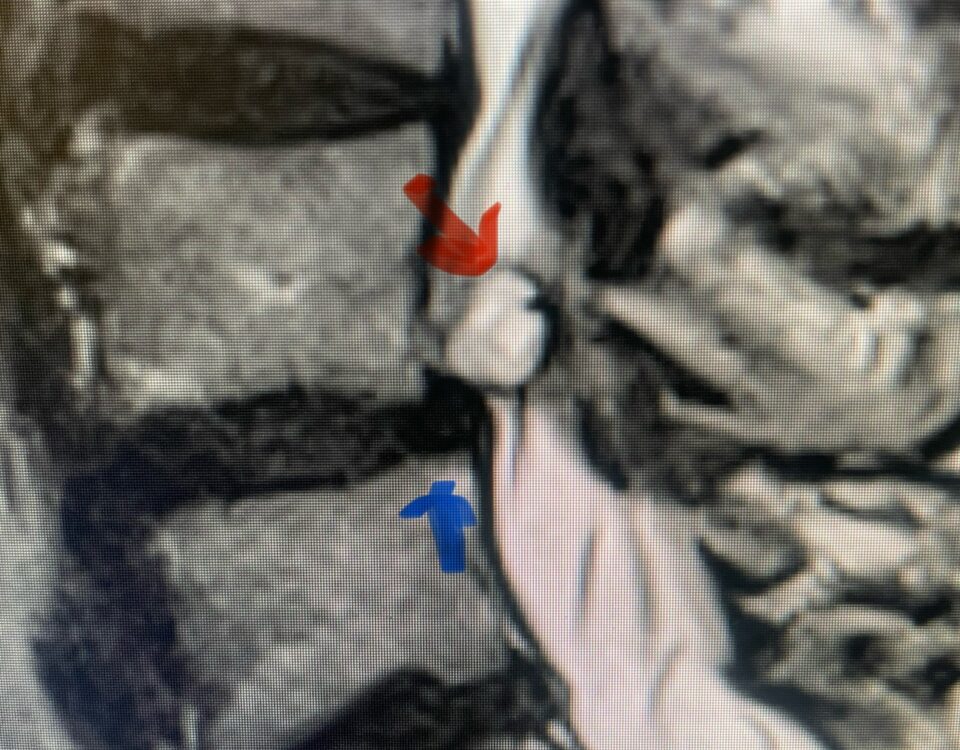

Here is a tough case: This is a 72 year-old male who presented with several months of progressive neck pain without symptoms of the arms or legs. […]